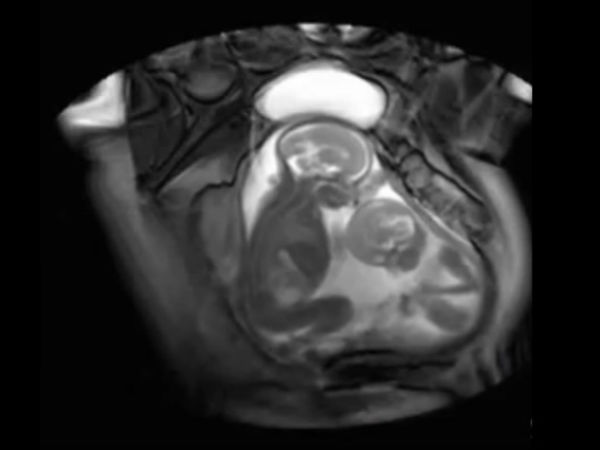

இரட்டையர்கள் பார்ப்பது என்றாலே ஆச்சரியமும், வியப்பும் தான். அதுவே அவர்கள் கருவில் அடித்து விளையாடுவதை பார்ப்பது என்றால்? இந்த காணொளிப்பதிவில் பாருங்கள்.

நம் வாழ்வில் சுவாரஸ்யங்கள் எப்போதாவது ஒருநாள் நடக்கும் என்றால். இரட்டையர்கள் வாழ்வில் மேகம் நம்மை கடந்து செல்வது போல, சுவாரஸ்யங்கள் நிறைந்த வாழ்க்கை. கருவறை தாண்டி உலகுக்கு வந்த பின் மட்டுமல்ல, கருவறையிலும் நாங்கள் படு சுட்டி தான் காட்டிக் கொடுக்கிறது இரட்டையர்களின் இந்த காணொளிப்பதிவு...

தாயின் கருவறையில் இருக்கும் இரட்டை சுசுக்கள், கருவில் வளரும் போதே ஒருவரை ஒருவர் அடித்து உதைத்து விளையாடி கொண்டிருப்பது போன்று காட்சிகள் கொண்டிருக்கிறது இந்த காணொளிப்பதிவு.

இந்த வீடியோ ஸ்கேனிங் செய்த பொது பதிவு செய்தது போன்று இருக்கிறது.

இந்த காணொளிப்பதிவில் இரட்டையர்கள் இருவர் அடித்து விளையாடுவது. ஒருவரை ஒருவர் மாறி, மாறி அடிக்க முயல்வது மிக தத்ரூபமாக இருக்கிறது. பிறந்த பிறகு அல்ல, கருவறையிலேயே நாங்கள் எங்கள் சுட்டித்தனத்தை துவங்கிவிட்டோம் என கூறுவது போல இருக்கிறது இந்த காணொளி.

இந்த காணொளிப்பதிவு உண்மையாகவே ஸ்கேனிங்கின் போது பதிவு செய்யப்பட்டதா? அல்ல கிராபிக்ஸ் உதவியால் உருவாக்கப்பட்டதா? என்ற கேள்விகள் மனதில் எழுந்தாலும். கருவில் வளரும் இரட்டையர்கள் ஒருவருடன் ஒருவர் விளையாடுவது உண்மையே என்கிறது அறிவியல்.